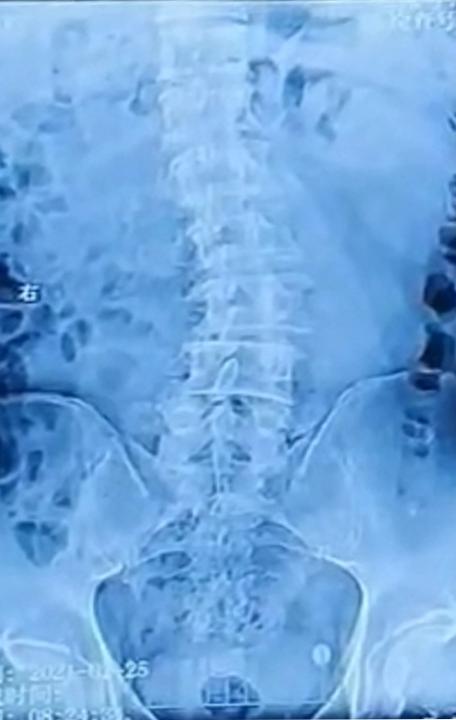

据廖博主任分析:从患者影像学检查上可以清晰地看到:腰椎的下腰区出现一个向左侧的侧凸,腰椎2/3、3/4、4/5都有不同程度的退变,但是在2/3、3/4退变相对来说,更加严重一些。在患者2/3、3/4两个节段,同时出现了轻度的滑脱,还有包括不同程度的椎管狭窄,我们可以把它分到b级或者c级,那么针对这样的病人,首先要考虑病人是否需要手术的干预。

关于刘大爷的治疗,廖博主任解释:我们为患者成功实施了腰椎斜前方入路椎间融合术后路经皮内固定术。给这位病人采取了三个节段的手术方案,放完三个cage以后的,术中的X片,可以看到,患者的退行性的侧凸,已经得到了很好的修正,那么从2/3、3/4和4/5三个节段的cage,冠状位的一个矫形,效果非常理想。

从这张片子上看,我们就可以很明确的看到手术前后在影像学上的变化,还是非常明显的。术后,刘大爷腰腿疼痛的症状消失,走路姿势也恢复正常。